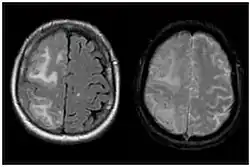

| Two MRI scans demonstrating the difference between ARIA-E (left) and ARIA-H in the parietal region (right) | |

Amyloid-related imaging abnormalities (ARIA) are abnormal differences seen in magnetic resonance imaging of the brain in patients with Alzheimer's disease. ARIA is associated with anti-amyloid drugs, particularly human monoclonal antibodies such as aducanumab.[1] There are two types of ARIA: ARIA-E and ARIA-H. The phenomenon was first seen in trials of bapineuzumab.[2]